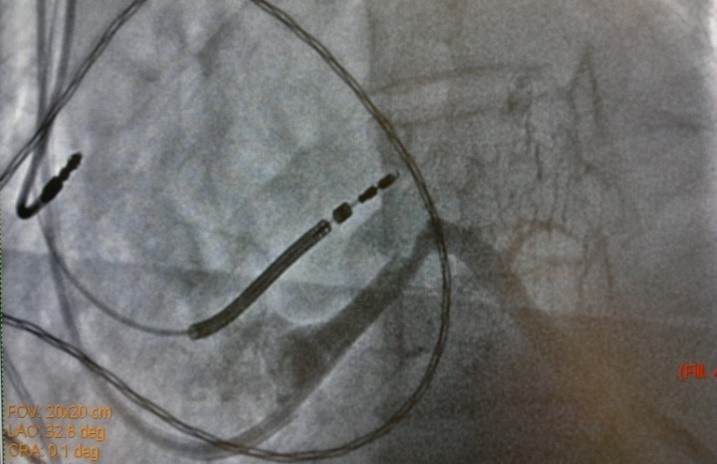

19.08.2015 выполнена попытка имплантации СРТ-D устройства, имплантировать ЛЖ электрод в заднею вену сердца не представилось возможным ввиду многократных смещений ЛЖ электрода в КС. Через 7 дней, вторым этапом, аритмологами и ренгенхирургами принято решение о имплантации ЛЖ электрода в заднюю вену ЛЖ с фиксирующим стентированием ЛЖ электрода в задней вене ЛЖ. Под м/а выполнен разрез в левой подключичной области по п/о рубцу. Выделен и выведен в рану ИКД. Пунктирована подключичная вена из раны. Желудочковый дефибриллирующий электрод активной фиксации позиционирован и вкручен в область МЖП 15 мV (с целью достаточного межэлектродного расстояния) [3], порог стимуляции желудочков 0,8 мА. В ПП по системе доставки доставлен катетер для КС, установлен в КС. Выполнена ангиография коронарного синуса (рис.1) – доступна единственная задняя вена ЛЖ, размером более 4 мм. ЛЖ электрод заведен через систему доставки и установлен в заднюю вену ЛЖ по коронарному проводнику. Порог стимуляции ЛЖ-2.0 мА, порог чувствительности 16.6 мВ. Стимуляции диафрагмального нерва нет. При попытке удаления системы доставки, последний дислоцируется в КС. Множественные попытки имплантации ЛЖ электрода безуспешны в связи с дислокацией последнего. При имплантации в дистальное русло порог ЭКС >6мА. ЛЖ электрод установлен в дистальное русло ЗВЛЖ по коронарному проводнику. Принято решение о фиксирующем стентирование ЛЖ электрода в ЗВЛЖ. Под м/а пунктирована v.f.s., установлен интродьюсер 6 Fr. К устью КС подведен проводниковый катетер JR4 6FR. В дистальное русло ЗВЛЖ проведен коронарный проводник (рис.2). По проводнику в ЗВЛЖ заведен стент 4.5-16 mm, выполнена имплантация (рис.3). При контрольной ангиографии диссекций не выявлено, стент расправлен полностью. Под контролем Rg-скопии и на раздутом баллоне удалена система доставки ЛЖ электрода, ЛЖ электрод стабилен (рис.4), порог ЭКС-0.8 мА (до стентирования 1,5 мА), сенсинг 10 мВ. Электроды фиксированы в ране. Подключен CRT-D и помещен в прежнее ложе над грудными мышцами. На ЭКГ эффективная бивентрикулярная стимуляция.

Рис.1. Рентгеновский стоп-кадр при контрастирование коронарного синуса. Диаметр «единственной» задней вены был более 4 мм и соответствовал диаметру коронарного синуса.